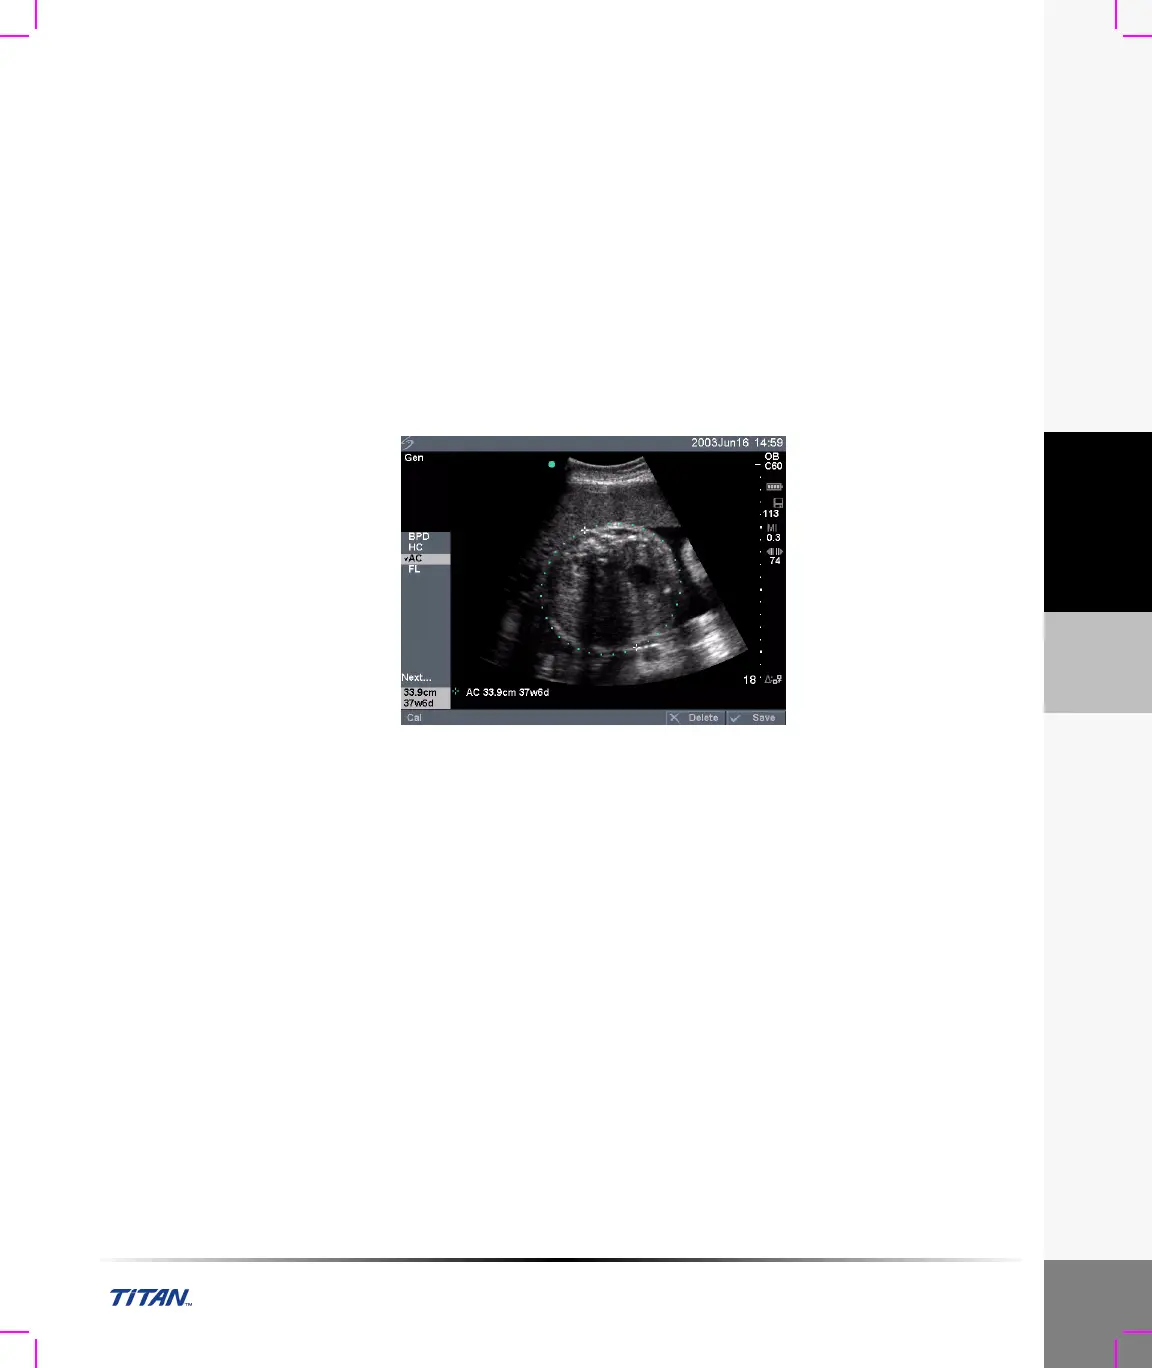

Figure 9 OB Measurement

Note 1: The Gestational Age is automatically calculated and displayed next to the OB measurement you

selected. The average of the results is the AUA.